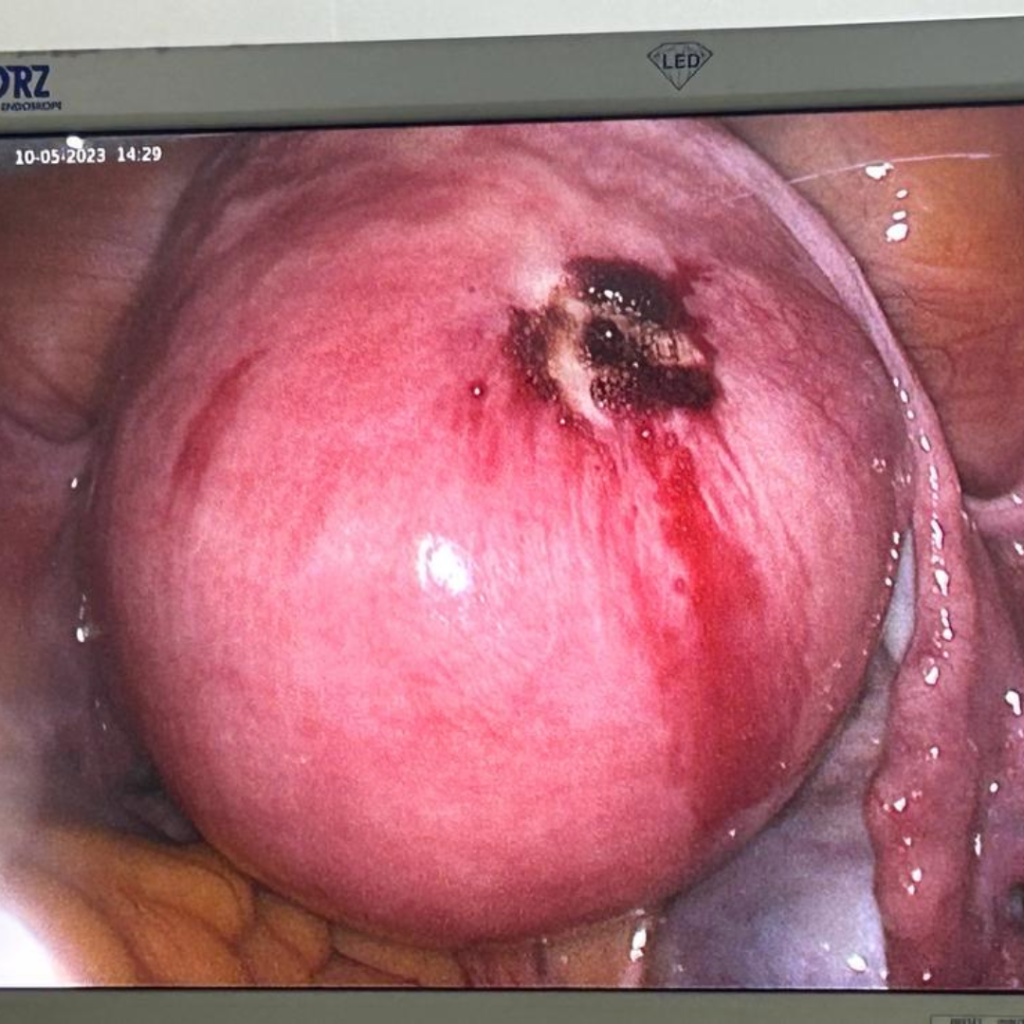

Laparoscopic Removal of Myoma in infertile couple